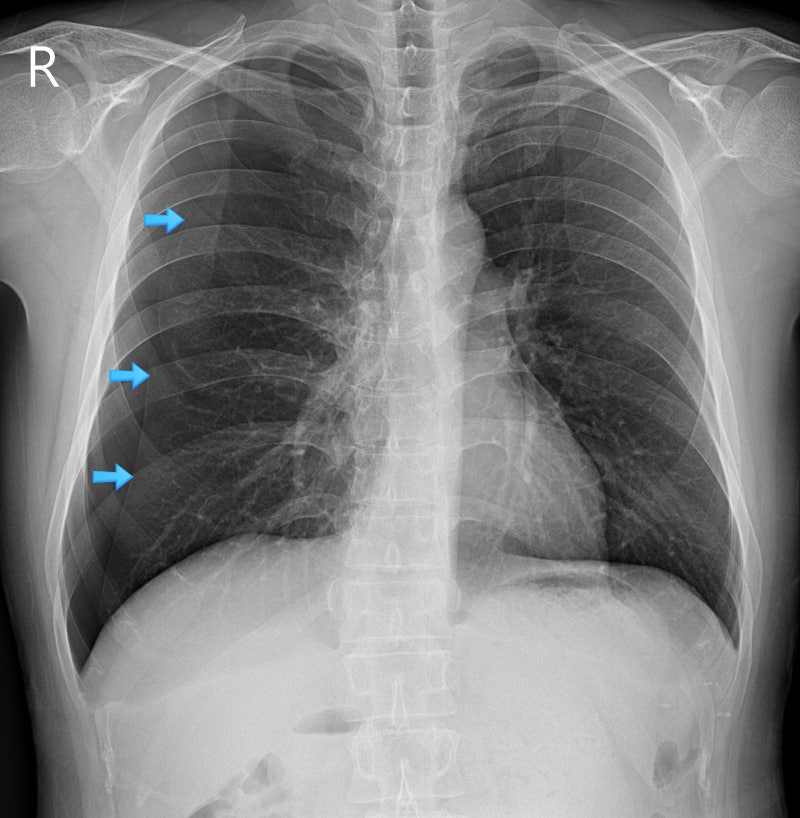

전유성 씨 사망 보도에서는 “폐기흉 증세 악화”라는 표현이 많이 등장했어요. 보통 “폐기흉”보다는 “기흉”이라는 표현이 의학적으로 더 일반적이고, 흉막강 내 공기가 유입되는 현상을 의미합니다.

✅ 기흉(폐기흉)의 정의

- 폐와 흉막 사이 공간(흉막강)에 공기가 유입되어 폐가 압박당해 팽창하지 못하는 상태

- 호흡곤란, 흉통 등을 유발할 수 있고, 심한 경우 응급 상태로 발전

- 자연발생형(자발성 기흉)과 외상성 기흉으로 나눌 수 있음